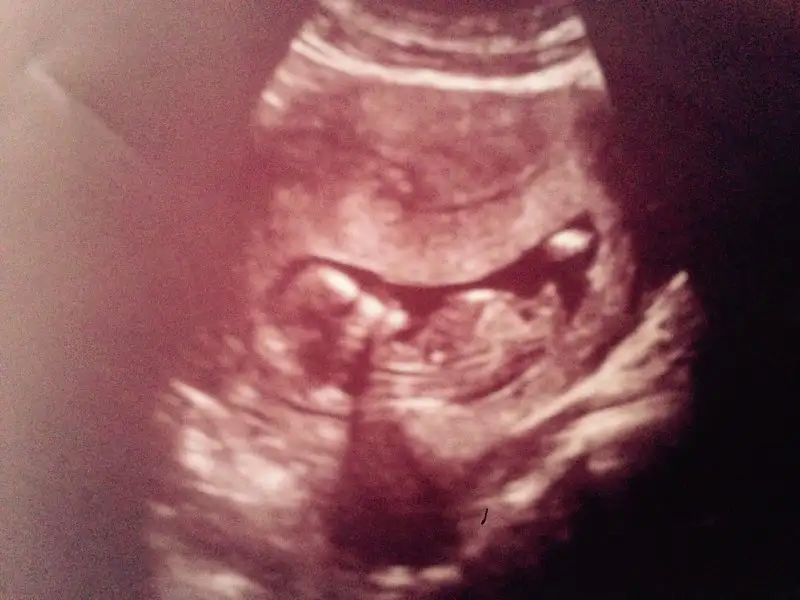

merhaba çok teşekkür ederimsana zahmet bir de buna bakabilir misin6 hafta 6 gün arkadaşımın karından

Eklentiler

• B4130C06-DA07-45FE-81CA-5ECA5529FC2D.webp

B4130C06-DA07-45FE-81CA-5ECA5529FC2D.webp

17,8 KB · Görüntüleme: 149